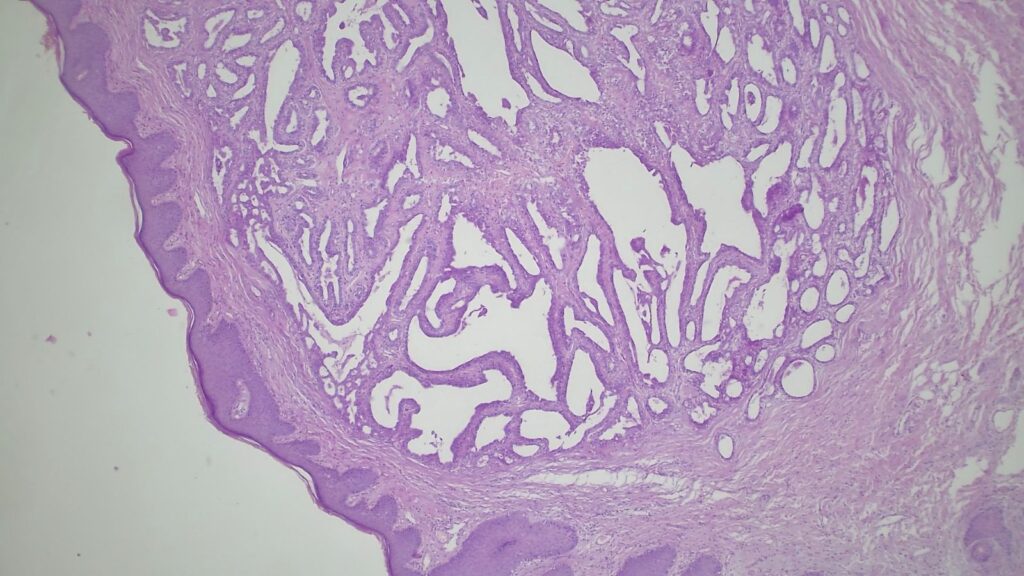

【临床背景:虚惊一场的“高分化腺癌”】 患者: 45岁女性,患有长期慢性肛瘘。 送检疑点: 组织学切片显示,在皮下异常位置出现了一个圆形的腺体增生灶。 考虑到病变的位置和形态,首诊团队和患者都极度恐慌,高度怀疑这可能是在瘘管内继发的高分化腺癌(Well-differentiated adenocarcinoma)。

【病理形态学大解密:寻找良性证据】 仔细阅片后,专家指出了以下几个至关重要的形态学特征(见附带病理切片图):

✅ 腺体发育良好,呈圆形和分叶状结构。 ✅ 边缘虽略不规则,但整体呈推挤性(pushing)和局限性生长。 ✅ 无弥漫性浸润结构。 ✅ 无促结缔组织增生性间质反应(No desmoplastic stromal reaction,这是排除浸润癌的核心点)。 ✅ 细胞学形态温和(Bland cytology)。 ✅ 在慢性炎症和纤维化的背景下,仅见单个典型的核分裂象。 在病变外周,腺体表现出被瘢痕样间质压迫和塑形的特征,而不是破坏性或浸润性生长。